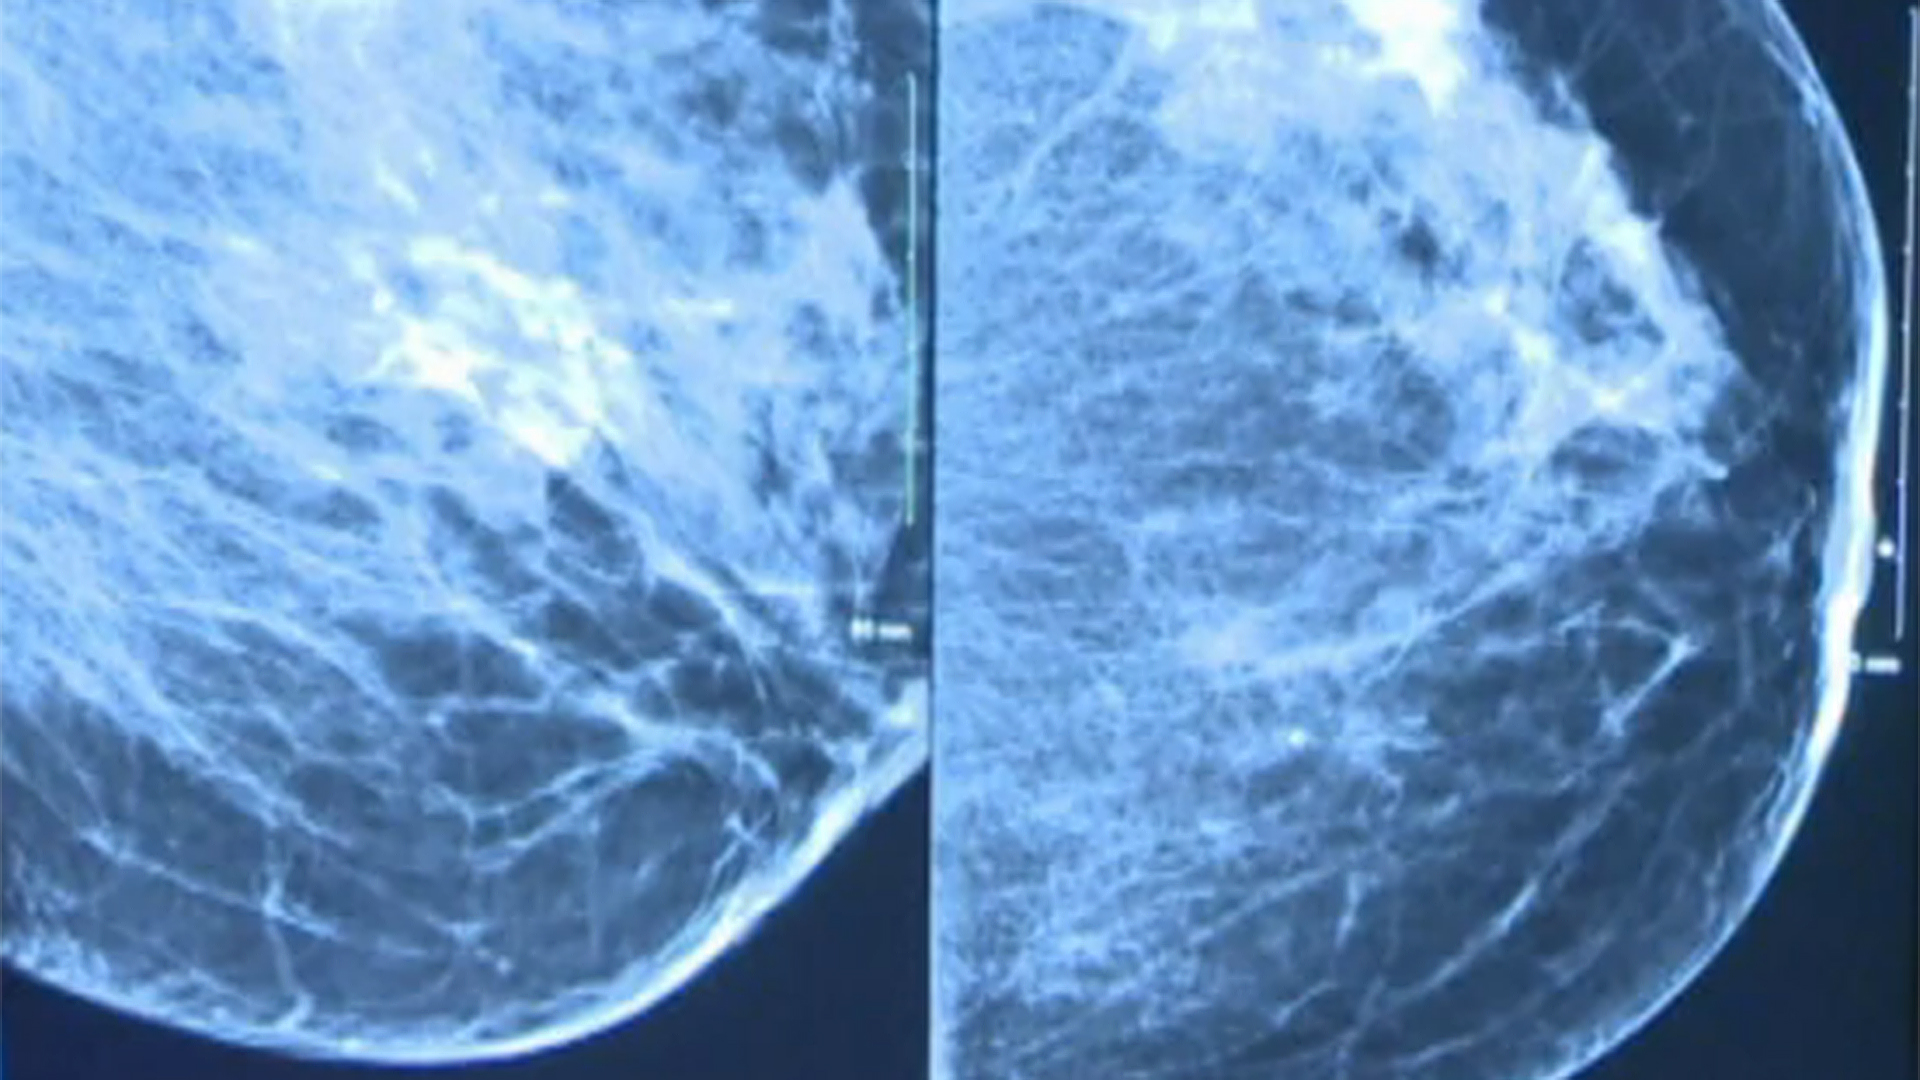

3D mammogramWhen you have your annual screening mammogram, the radiologist—a doctor with specialized training to read and interpret such images— examines your mammogram and then sends a report to your referring physician. But how do radiologists interpret what they see in mammography images? Today, we’ll give you a glimpse into the types of features and patterns on mammograms that cause radiologists to take a closer look.

Your mammogram report will also document your breast density, based on how much of your breast tissue is made up of fibrous and glandular tissue compared to fatty tissue (less fatty tissue = denser breasts). Dense breast tissue is not an abnormality, but it may indicate a higher breast cancer risk and make irregularities more difficult to spot on your mammograms. Be sure to discuss any risk associated with your breast density with your referring physician to develop the most appropriate plan for your care.